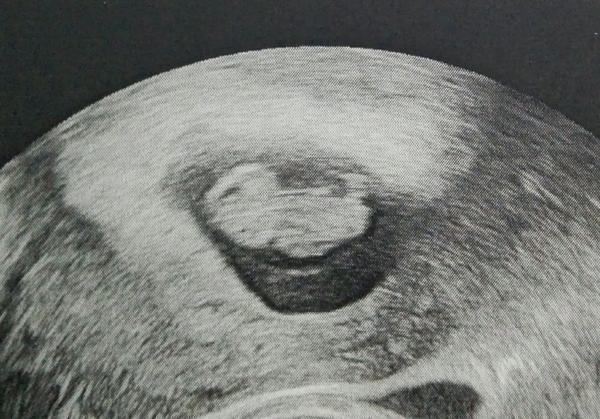

Tak sa ideme pochváliť, 9+0 a cca 2 cm 💞

@dolynkag aka krasna fotečka🙂,len tak dalej sa držte